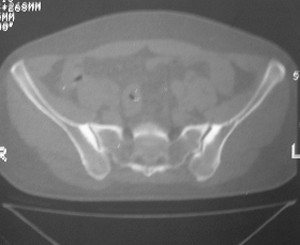

标题: CT7246: F,30岁,下腰痛,同事的片子,请老师们看看,初 [打印本页]

标题: CT7246: F,30岁,下腰痛,同事的片子,请老师们看看,初

典型的致密性髂骨炎

典型的双侧骶髂关节致密性骨炎.

何谓髂骨致密性骨炎?髂骨致密性骨炎是发生于髂骨耳状关节部分的骨质密度增高性疾病。病因迄今不明,可能与妊娠、机械性劳损、病灶性炎症有关。本病好发于20~35岁的育龄妇女,偶见男性。

髂骨致密性骨炎的临床表现与体征:腰骶部疼痛,多呈慢性、间歇性酸痛、隐痛,可向一侧或双侧臀部及大腿后侧扩散,但不沿坐骨神经方向放射,步行、站立、负重及劳累后加重,咳嗽、打喷嚏不能使疼痛明显加重,休息后症状减轻。患者腰骶角加大,局部有压痛和肌紧张,骨盆分离和挤压试验阳性,“4”字试验阳性,化验检查多在正常范围内。x线检查,骶髂关节间隙整齐清晰,靠近骶髂关节面中的髂骨耳状关节部分骨质密度增高,呈均匀浓白边缘清晰的骨质致密带,骨小梁消失,无骨质破坏。本病应注意与早期强直性脊柱炎、骶髂关节结核相鉴别。